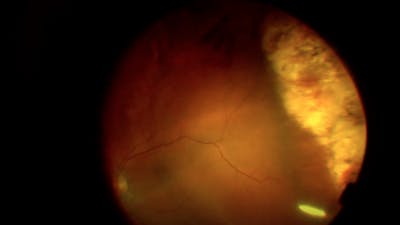

Maria Berrocal, MD and Maggie Runner, MD

Maria Berrocal, MD; and Katherine Talcott, MD

Barton Blackorby, MD, Katharine Talcott, MD, and Hong-Uyen Hua, MD